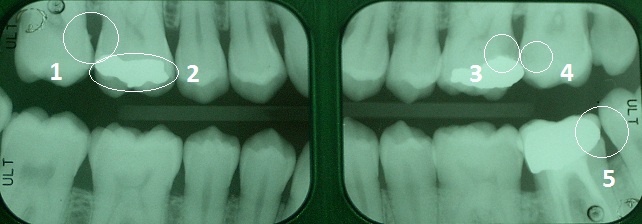

RADIOGRAFIE BITE WING

Le radiografie Bite Wing sono delle normali radiografie endorali che l'odontoiatra utilizza con una speciale tecnica di posizionamento orale in modo da ottenere, con solo due radiogrammi, un quadro diagnostico di primo livello molto esaustivo delle condizioni del paziente e delle patologie in atto nei settori posteriori.

Da questo esame si possono trarre numerose informazioni:

- Stato delle corone dentali

- Stato dei restauri conservativi (otturazioni) (2)

- Stato dell'osso

- Presenza di tasche ossee

- Presenza di impianti

- Lesioni cariose primarie (4)

- Lesioni cariose secondarie (3)

- Spicole di pericolosissimo tartaro sottogengivale (1)

- Restauri protesici con margini incongrui (5)

.